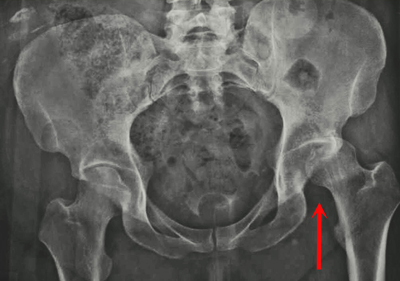

This x-ray, taken from the front, shows a patient with a posterior dislocation of the left hip.

Your doctor may order imaging tests, such as x-rays, to show the exact position of the dislocated bones, as well as any additional fractures in the hip or thighbone.